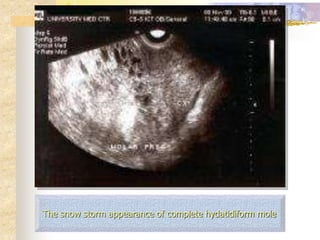

 Ultrasonography:

* The diagnosis of molar pregnancy is nearly always

made by ultrasonography

Complete mole

•The classical finding is a

“snow storm" pattern

The snow storm appearance of complete hydatidiform mole